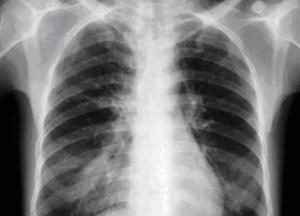

Медики назвали ранние признаки рака легких

При начальной стадии рака легких появляются ранние признаки данного заболевания. Учёные из Великобритании проанализировали «странности» на коже в виде появления «синюшных» или фиолетовых пятен, передает FaceNews.ua.

Исследователи заявляют, что имеется несколько явных внешних признаков опасного онкологического заболевания, поражающего в том числе органы дыхания. Следует обращать внимание на кожную сыпь, появляющуюся беспричинно. В данном случае необходимо пройти обследование у профильных врачей. «Странные» высыпания происходили в ряде случаев у пациентов, у которых впоследствии диагностировали рак лёгких. Далее следует опущение века. При названном недуге поражается часть органа, через который проходит основное количество нервов, в том числе отвечающих за состояние глаз и некоторых сегментов лица.

Вслед за этим называют необъяснимую обильную потливость, которая может являться ещё одним внешним признаком возникшего рака лёгких. Как правило, заявляют специалисты, опухоль находится на той стороне, где лицо потеет меньше. Симптомом опасного заболевания являются также уменьшение зрачка и появление хрипоты, что может указывать на поражение голосовых связок.